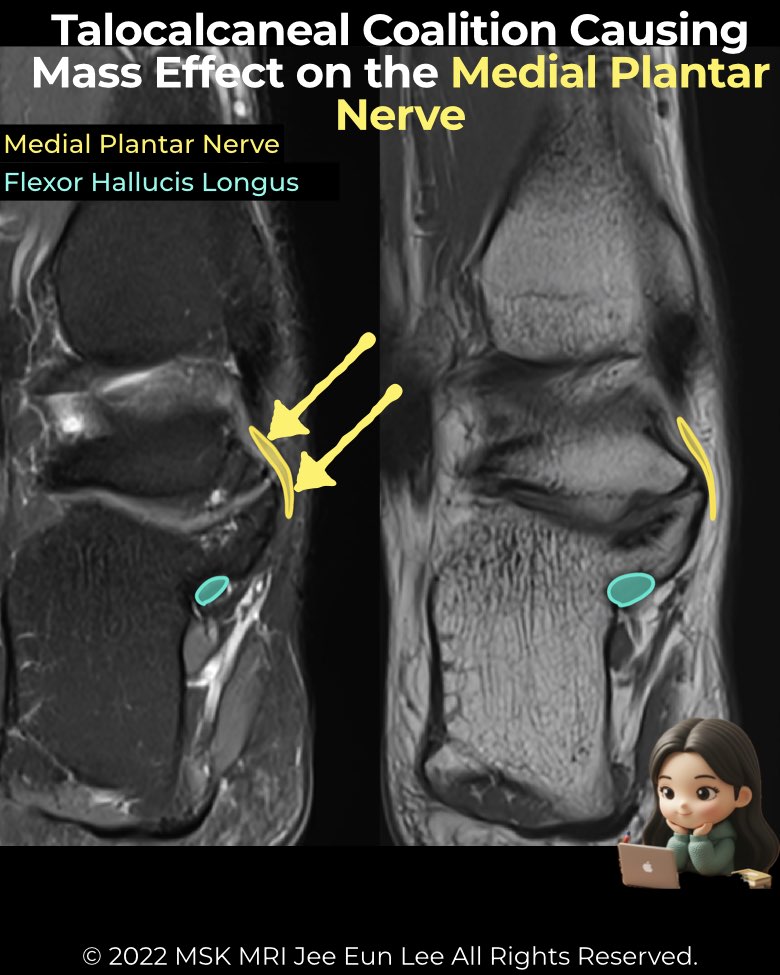

Tarsal coalitions, especially talocalcaneal types, can produce mass effect in the tarsal tunnel, leading to nerve and tendon pathology.

- Bony overgrowth from fibrous/cartilaginous coalitions (often EA-PM or middle facet) protrudes into the tunnel.

- The medial plantar nerve (MPN) is most frequently affected due to its close course along the medial talus/calcaneus.

- MRI findings of neuritis:

• Focal T2 hyperintensity (equal to or > blood vessels)

• Caliber enlargement

• Direct abutment/displacement by coalition or cyst